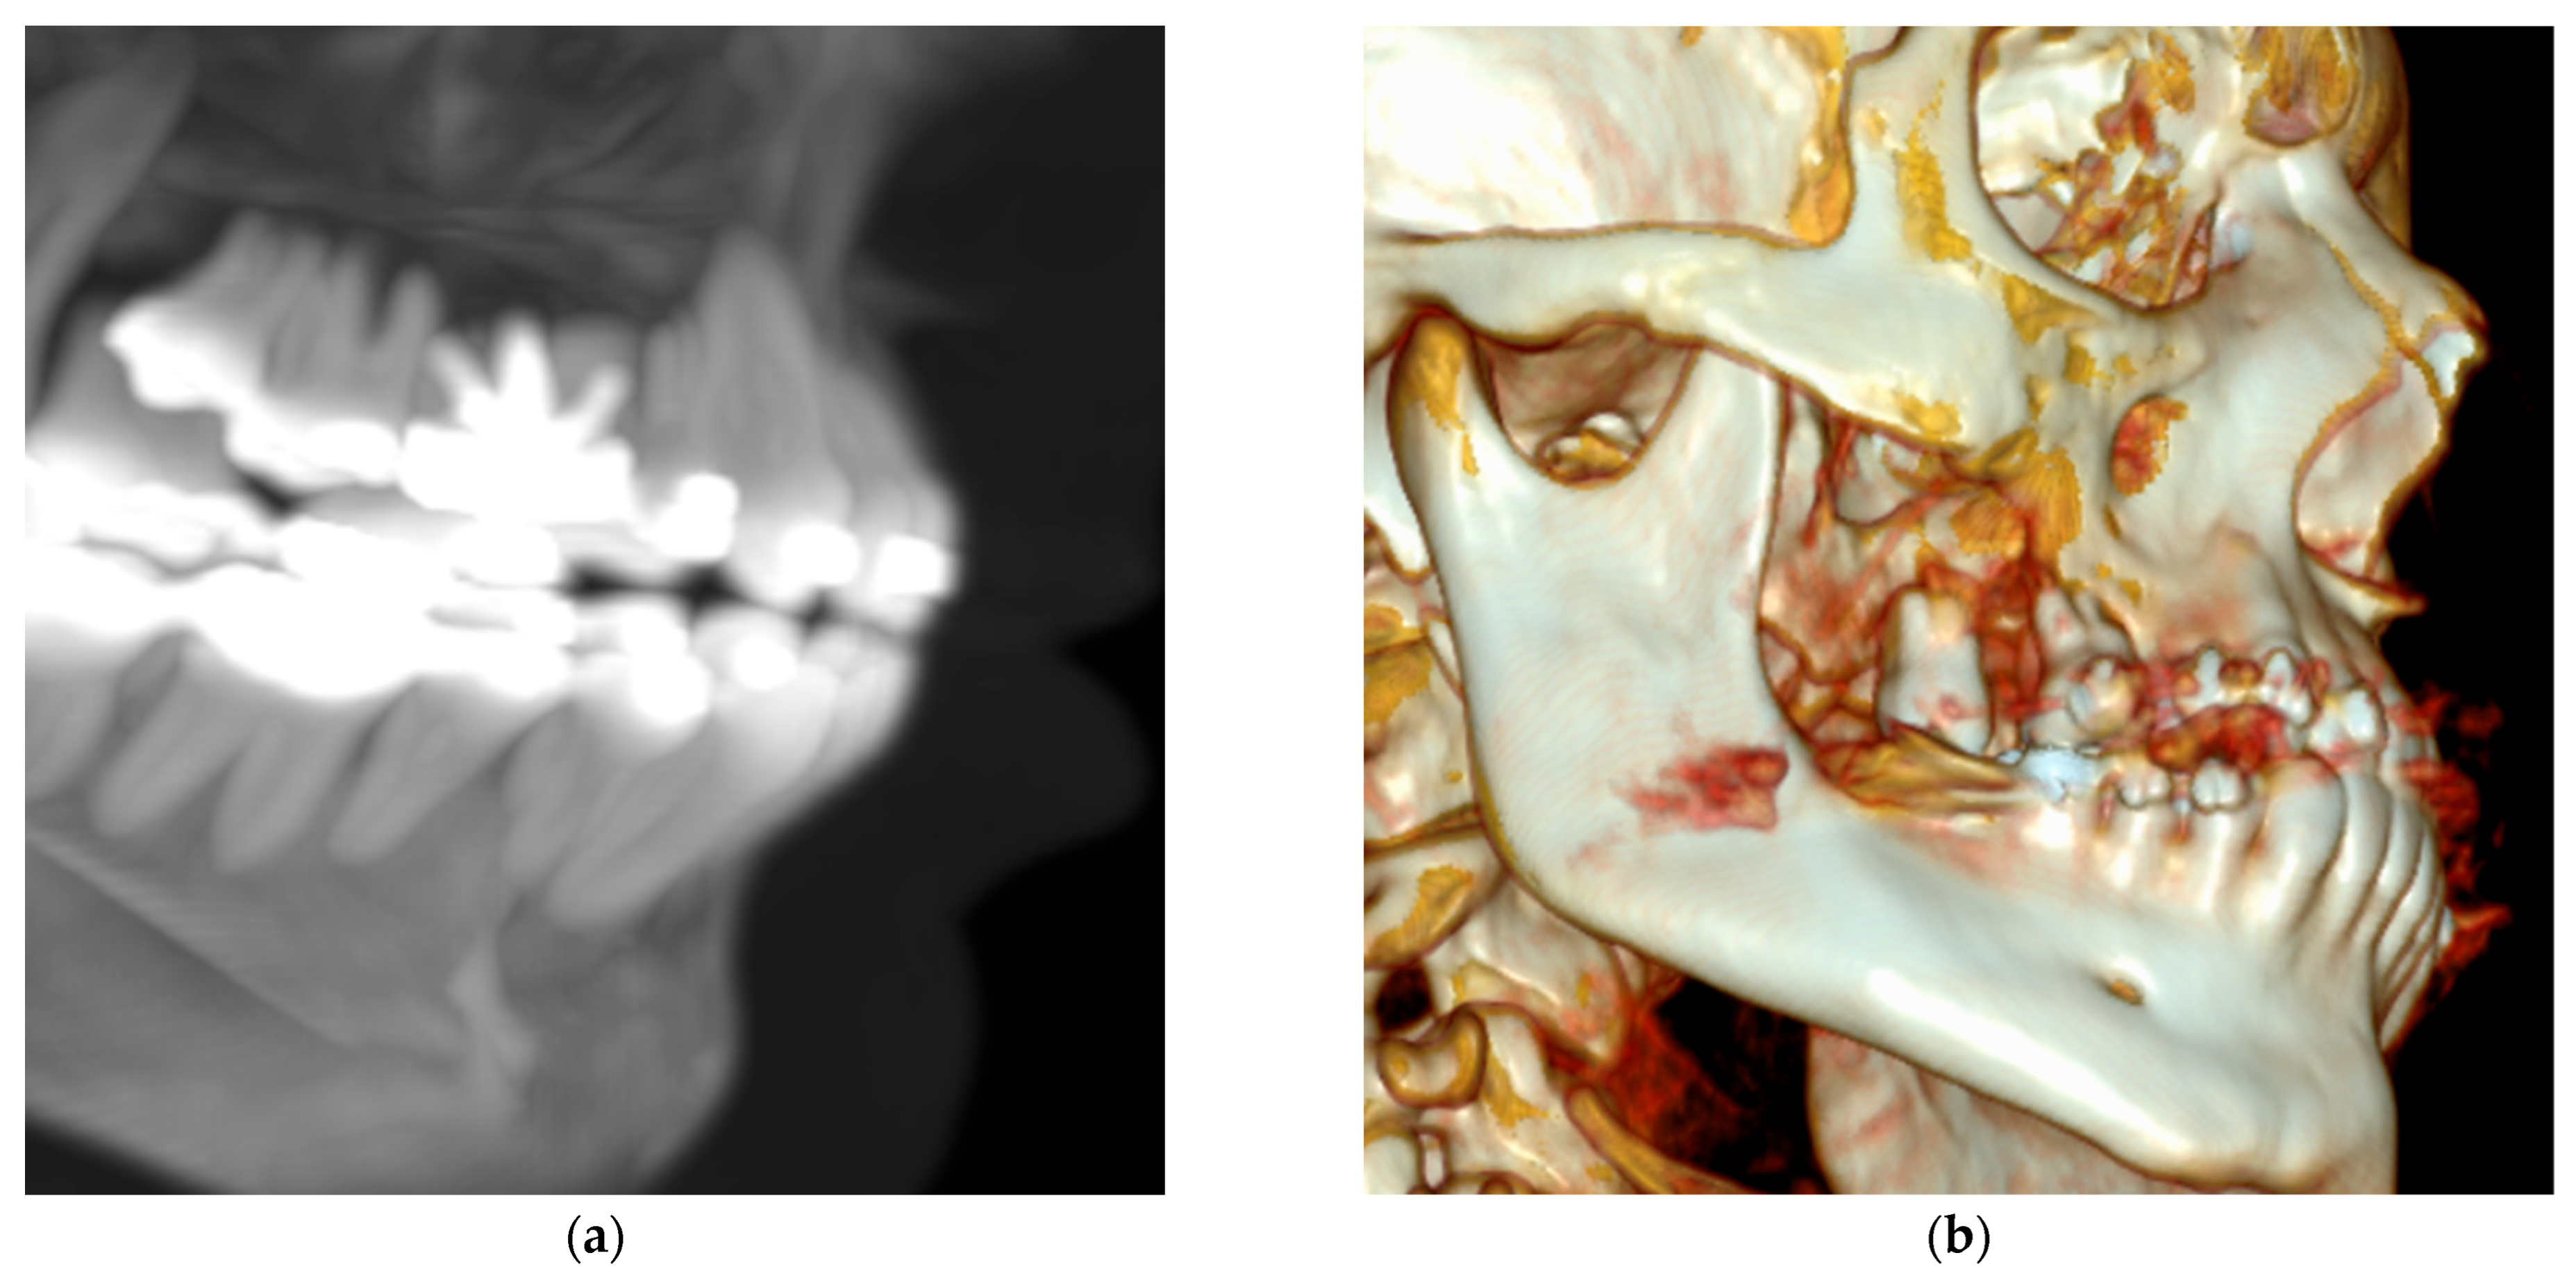

Figure 2.

Contrast-enhanced computed tomography (a) Axial slice reveals an isodense area relative to soft tissues with hyperenhancing central regions, show prominent vascularization. (b) Coronal view revealing elevation of the right maxillary sinus associated with the maxillary first molar. (c) Sagittal view illustrating in greater detail the sinus elevation and regions of hyperenhancement.